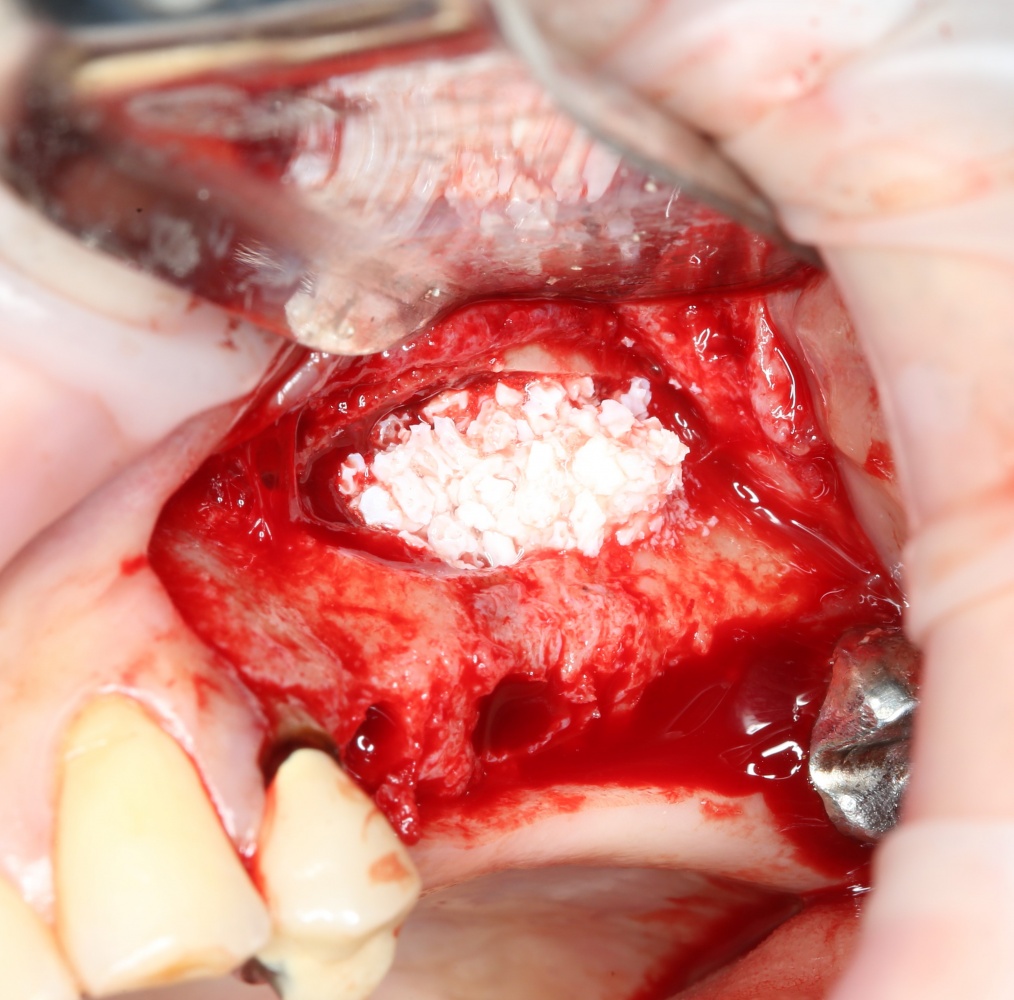

Однако, в этот раз я решил немного изменить план лекции. Теперь свою часть каждого из семинаров я буду посвящать какой-то конкретной операционной методике, рассказывая о ней чуть подробнее, чем принято говорить «бесплатно». И начнём мы с синуслифтинга, самой распространенной остеопластической операции в мире.

О том, почему открытый синуслифтинг безопаснее закрытого. И почему при закрытом синуслифтинге я не рекомендую использовать биоматериалы:

Каковы показания к открытому синуслифтингу? Когда его можно проводить совместно с установкой имплантов. а когда лучше сделать отдельным этапом?

Как правильно и аккуратно сделать доступ в верхнечелюстную полость? И как создать достаточное по объёму субантральное пространство?

Как выбрать графт для заполнения субантрального пространства? И на какие свойства графта нужно обратить максимум внимания?